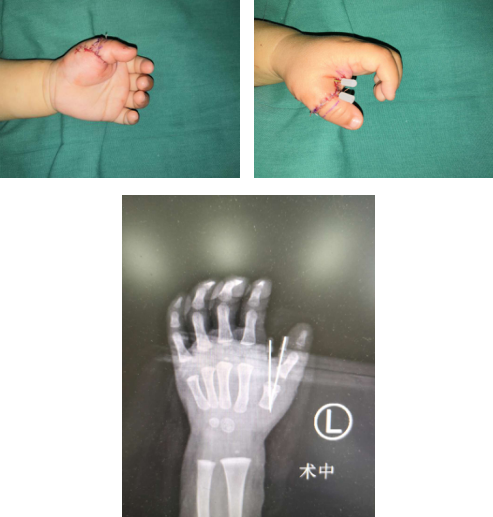

乐乐出生时,爸爸妈妈发现她的左手多了一根手指,当时他们的心情非常低落、沮丧,多次到医院就诊,被告知乐乐的左手复拇指畸形,需要手术治疗。两年来,经过多方打听,他们了解到betway在线登陆手外科对于先天性手部畸形有非常丰富的治疗经验,于是赶紧带着孩子来到了医院。在第一次见到乐乐的妈妈时,我就明显感觉到她的焦急与期待,乐乐也非常不情愿地伸出自己的左手给我检查。经过检查发现乐乐的手部畸形为复拇指畸形,属于Wassel VII型,桡侧指为三节拇,末节纤细、偏斜、外形差,尺侧多指外形好,但虎口狭窄、拇指指体向尺侧偏斜。我安慰乐乐的爸爸妈妈不要担心,很多比乐乐情况更为复杂的畸形患儿都得到了很好的矫形。

术前

当天下午,我们为乐乐制定了细致的手术方案,手术主要将复拇指畸形有明显优势的拇指保留,将外形差的拇指去除,第1掌骨头下楔形截骨,克氏针内固定,修复了掌指关节韧带、重建拇短展肌止点,改善了患手功能及外形。乐乐的爸爸妈妈对于手术表示满意,出院时再一次感谢了我们。

术后即刻